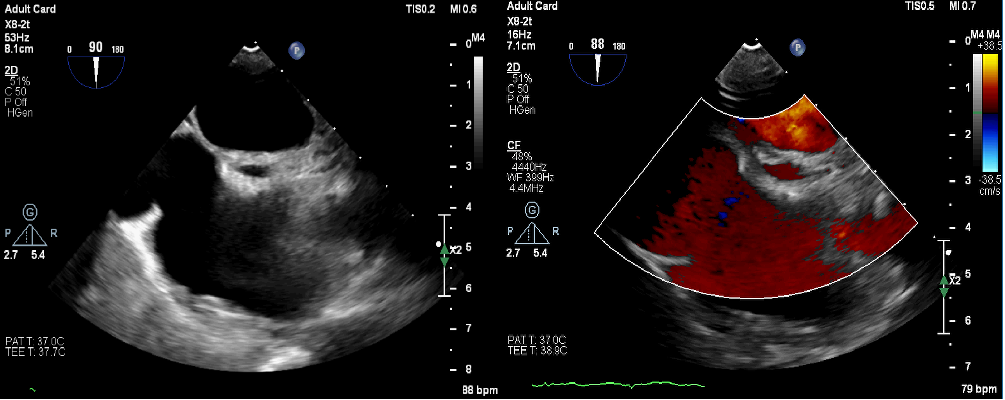

A 48-year-old man was admitted to our hospital with typical symptoms of TIA. Preoperative transesophageal echocardiography demonstrated PFO (Figure 1) and secondary septal pouch on the right (Figure 2, Video 1). Contrast transthoracic echocardiography (TEE) showed a moderate right-to-left shunt (Video 2). To close the secondary septal pouch and the PFO at the same time, successful atrial septal puncture was confirmed under the guidance of TEE (Figure 3A). Subsequently, a 25/25-mm Cera ASD occluder (LifeTech Scientific) was implanted (Figure 4). Post-implantation, the occluder was stable at the implant location (Figure 3B-D). Furthermore, the right-to-left shunt disappeared immediately (Video 3). Thus, ASD occluder implantation may be an effective simultaneous treatment of PFO and secondary septal pouch.

Figure 2. (A) The secondary septal pouch was visualized on the right atrial septal with an area of about 11.7 x 4 mm2. (B) Visualization of the blood inflow into the secondary septal pouch.